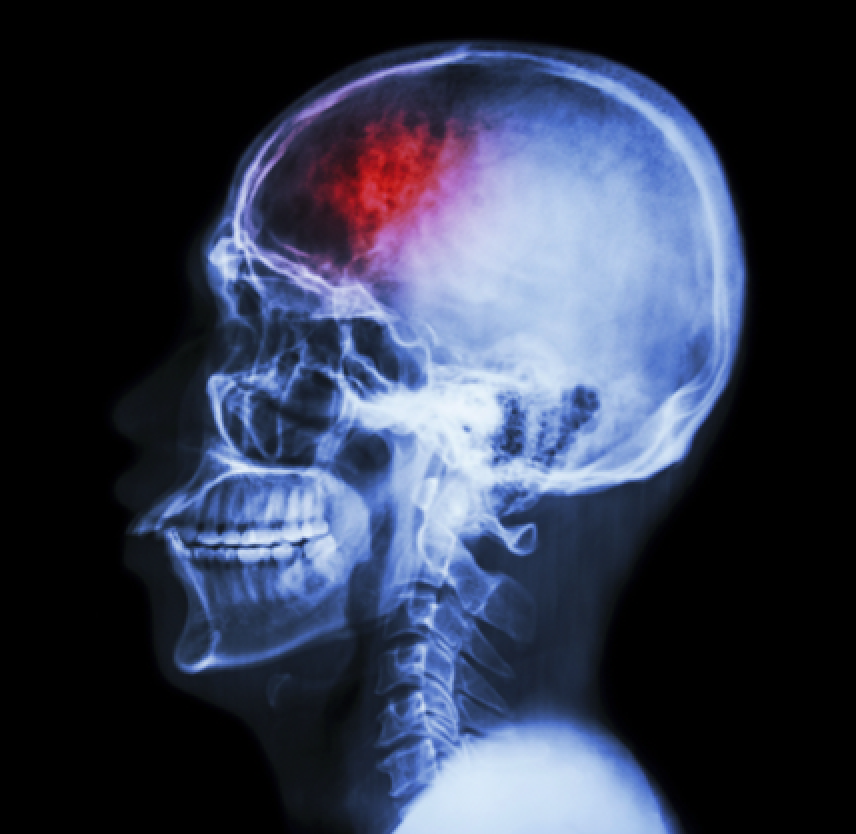

What exactly is a traumatic brain injury?

Our brains are terribly fragile and vulnerable to all sorts of injury. Although brain tissue can be damaged by a variety of things like infections, tumors, or strokes, any injury to the brain from an external force results in a TBI.

Both types of TBI can result in bruised brain tissue, bleeding inside the brain, large or small lacerations in the brain, and nerve damage due to shearing forces. The brain can also experience a number of secondary types of damage, like swelling, fever, seizures, or an imbalance of neurological chemicals.